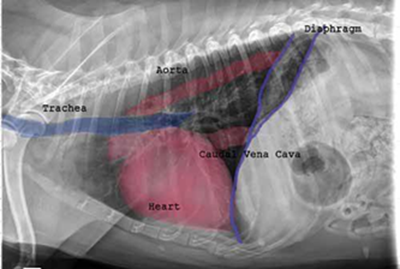

As noted above, what is not visible outwardly, before the dog reaches heart failure, is enlargement of the left chambers of the heart. As greater quantities of blood leak through the damaged mitral valve from the left ventricle back into the left atrium, the thin-walled atrium gradually begins to swell and enlarge (see x-ray image of a severely enlarged left atrium, outlined in red, above) -- called remodeling or cardiomegaly or dilation -- to accommodate the overload of blood, and there is a reduction in the ability of the left ventricle to provide sufficient blood to meet the demands of the rest of the body. The heart then has to pump harder and faster, to meet those demands. The shut-down of the distant blood vessels also has the effect of causing the left ventricle to beat against a higher resistance, causing another increase in mitral valve leakage.

Radiography (x-ray) is used to determine if the heart is enlarged

(particularly the left atrium and left ventricle), if the veins from the

lungs to the heart are distended, or if fluid is beginning to develop in the

lungs.* X-rays also will show any enlargement of

the pulmonary vein, a classic symptom of congestive heart failure (CHF).

• Using radiography to diagnose heart enlargement

Mild to moderate heart enlargement indicates mild to moderate progression of mitral regurgitation (MR), with the heart compensating for the effects of mitral regurgitation by enlarging. Usually the dog displays no outward signs or symptoms of MVD when moderate to severe heart enlargement develops, until the dog reaches the stage of heart failure.

• VHS measurements to detect enlargement

Cardiologists use x-rays to evaluate the size and shape of the heart in

order to assess the severity of MVD.

The Vertebral Heart

Size or Scale or Sum (VHS) is an objective means of measuring

heart size.

As

the x-ray image above shows, using calipers, they

measure the length (from the apex to the bottom of the left mainstem) and width

(at

its widest point perpendicular to the lemgth measurement) of the heart

on a lateral x-ray and compare those dimensions

to the number of veterbrae from T4 to T12, to calculate the VHS value. Since

the dog's own vertebrae are used for comparison, each VHS value is

normalized to the dog's overall body size.